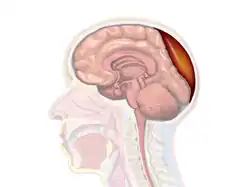

Nontraumatic epidural hematoma in a young woman. The grey area in the top right is organizing hematoma, causing midline shift and compression of the ventricle.

A diagram showing an epidural hematoma.